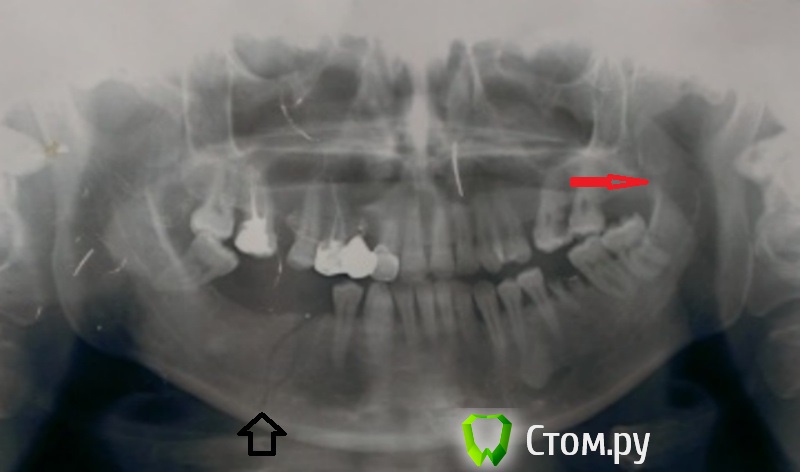

Ренат Бахитжанович Опубликовано 25 января, 2014 Поделиться Опубликовано 25 января, 2014 хирурги все сюда,всем привет!о великие surgeon,то есть хирурги!я в хирургии не проф.поэтому заранее сорри,ситуация такова-друзья,сегодня-пришла-пациентка,девушка лет 30,в канун нового года хорошо отмечала судя по диагнозу,она сломала себе челюсть сама,упав на асфальт,ну эт. по её словам,перелом был в двух местах,если видно-по рентгену.к врачам обратилась на следущий день,после появления отека и болей!врачи приняли её,зашинировали ей зубы,и вот спустя 25дней ей сняли шины,и она пришла ко мне!визуально выраженная ассиметрия лица,с права на н.ч-проработать,при пальпаций на ощуп плотное оброзование,при надавливание не значительно-болезненно.пациент рот до конца не открывает,разговаривает не много по другому!))теперь-скажите-что это и как-его лечить,если выложил-мало-инфо,не судите,молодой,еще зеленненький,а лучше дайте совет Ссылка на комментарий

эльдар дантист Опубликовано 25 января, 2014 Поделиться Опубликовано 25 января, 2014 Плотный инфильтрат и ассиметрия это костная мозоль скорее всего, ограничение открвания - почти всегда после шинирования из-за долгой дисфункции ВНЧС .... Вобщем если нарушения прикуса и выраженной подвижности отломков нет то все вроде ничего должно быть.....если при пальпации инфильтрата имеются выделения из парадонтального кармана гнойного характера- проверить нет ли зуба в линии перелама... Если есть удалить 1 Ссылка на комментарий

ILGAMSA Опубликовано 26 января, 2014 Поделиться Опубликовано 26 января, 2014 http://s019.radikal.ru/i601/1401/60/f1f8737f6fcc.jpg помимо явной линии перелома справа можно заподозрить еще 2 перелома. А может даже больше. Ссылка на комментарий

АнтонТЛТ Опубликовано 26 января, 2014 Поделиться Опубликовано 26 января, 2014 Еще можно заподозрить правую ветвь Ссылка на комментарий

kriokov Опубликовано 26 января, 2014 Поделиться Опубликовано 26 января, 2014 (изменено) снимок говно, конечнов обл тела слева похоже на один перелом, просто по плоскости с язычной и вестибулярной поверхности по разному линия\На перелом в обл ветви слева (венечный смущает) походит сильно, рот тогда туго открываться будет. переделайте снимки Изменено 26 января, 2014 пользователем kriokov Ссылка на комментарий

Maxfac Опубликовано 26 января, 2014 Поделиться Опубликовано 26 января, 2014 А отмечает ли мадам изменения со стороны прикуса? Вообще, судя по этому снимку, перелом в области тела без смещения. 2 Ссылка на комментарий